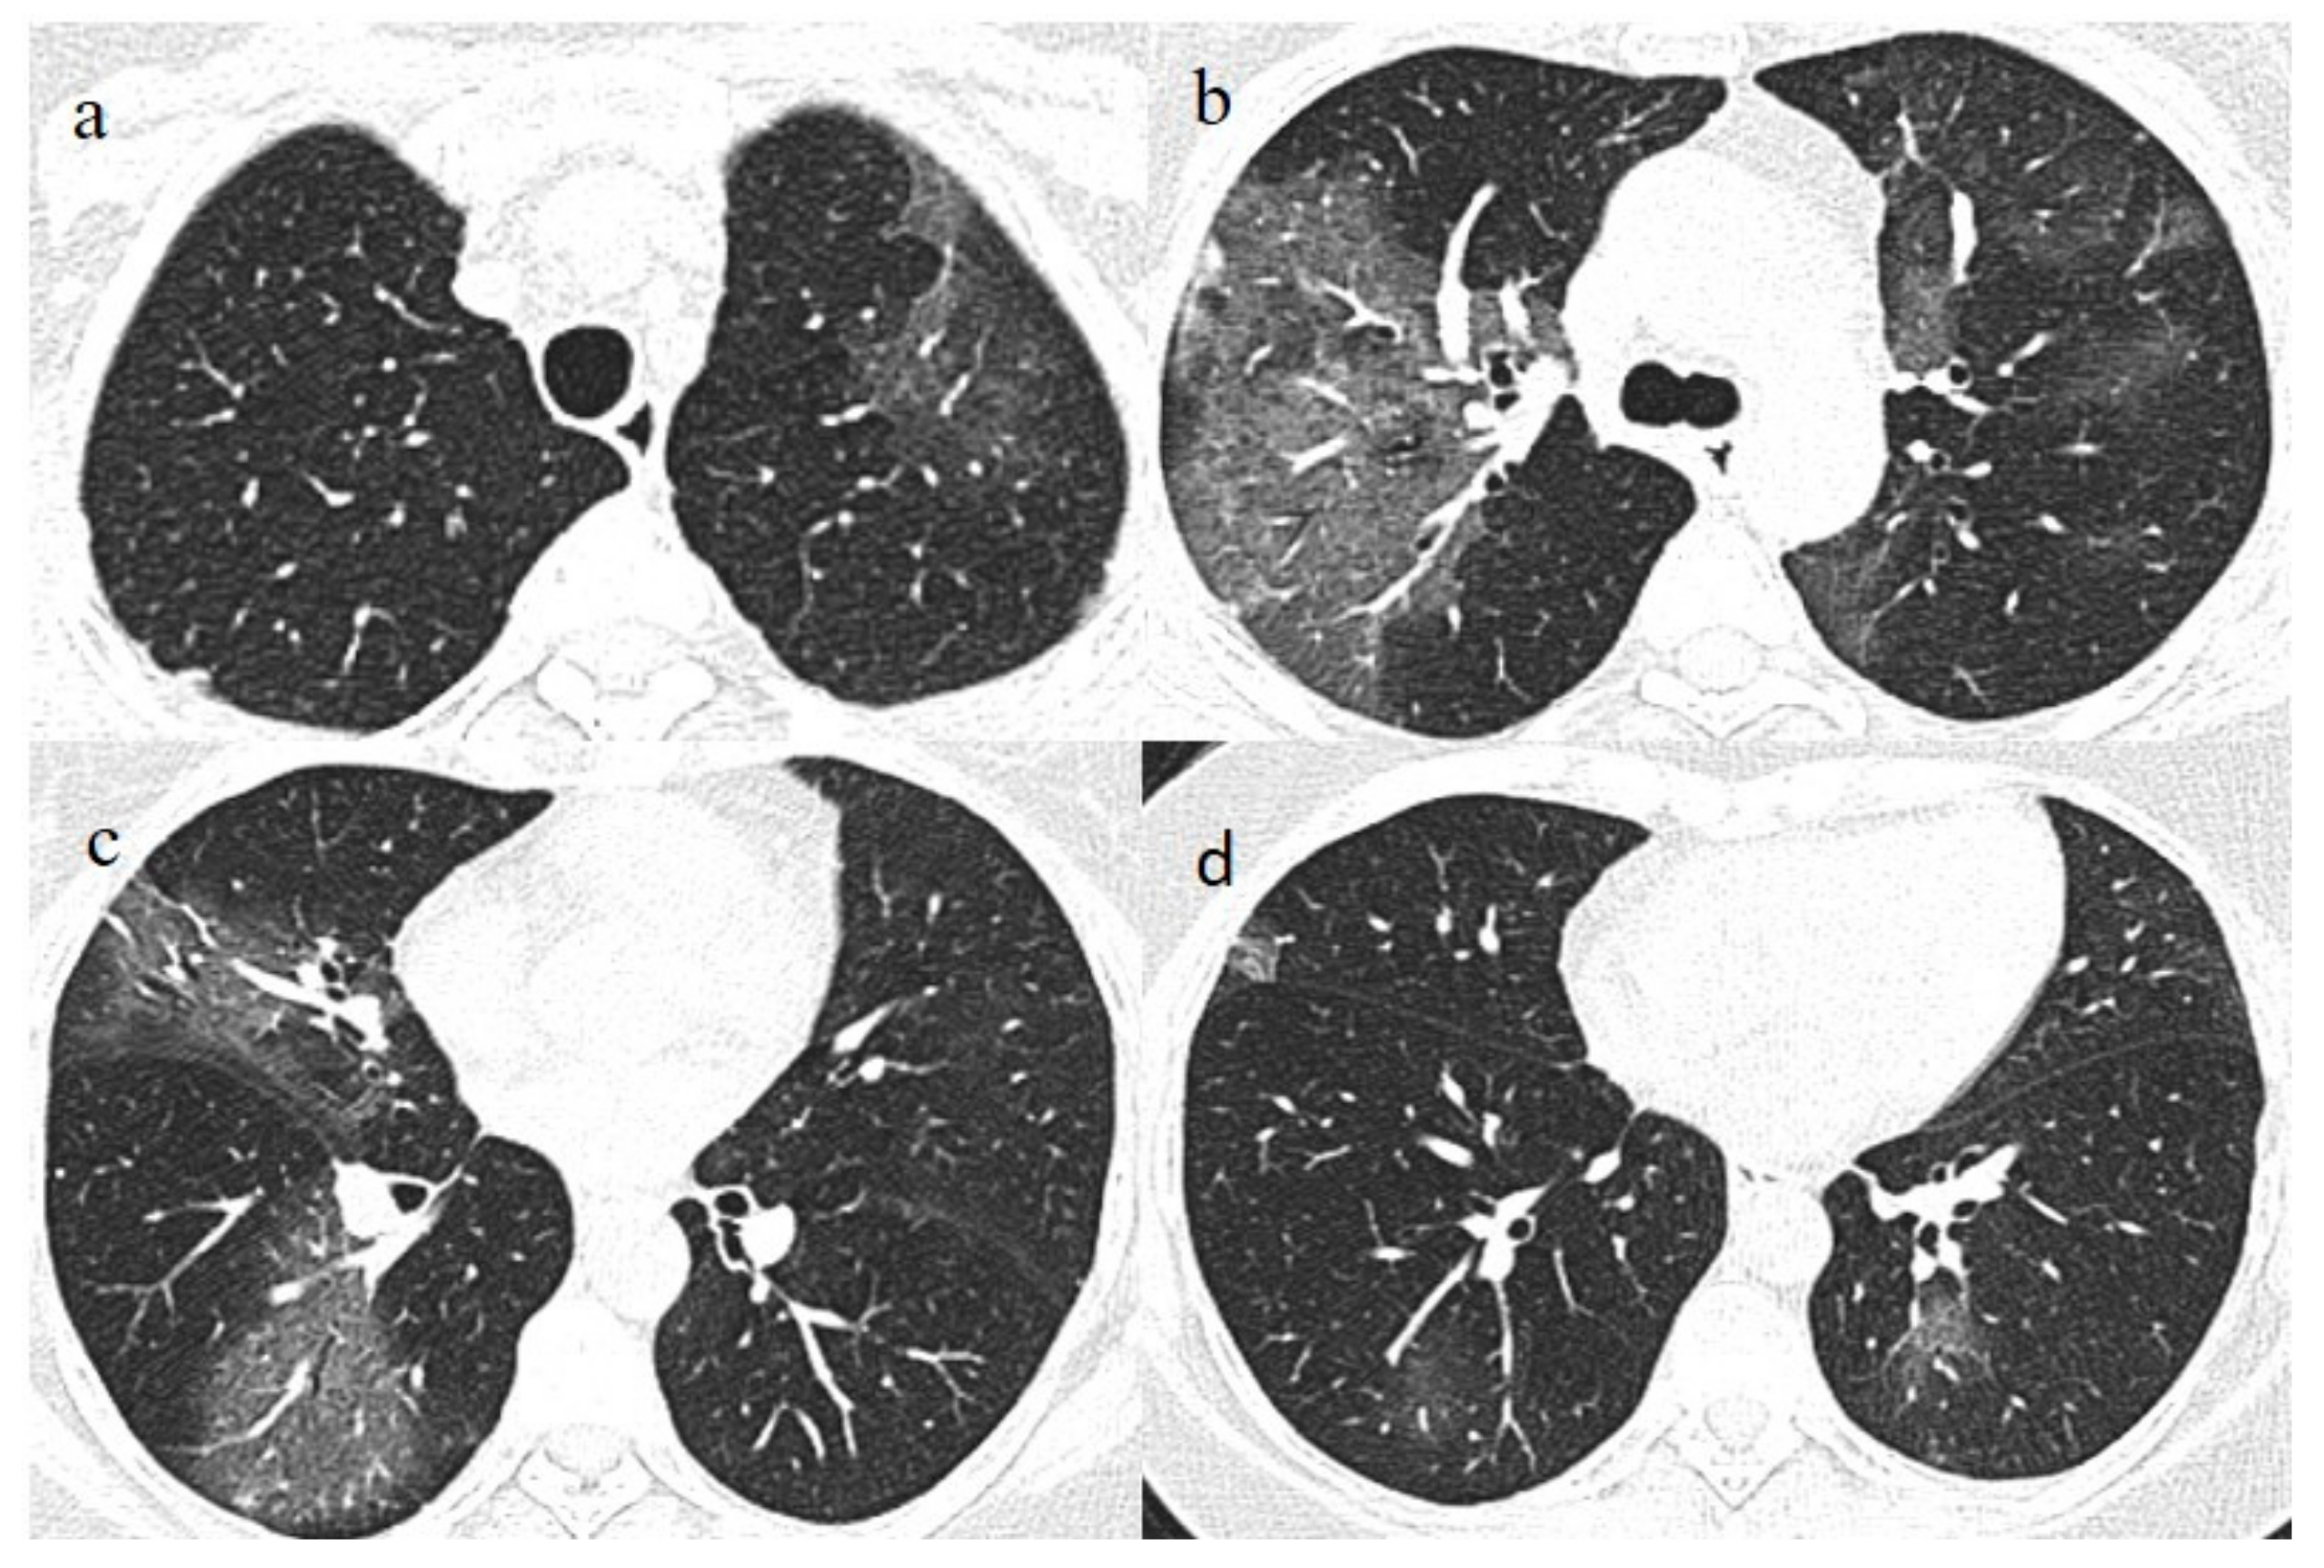

A 51-year-old woman with a history of follicular lymphoma in remission in September 2020, and with a previous SARS-CoV-2 infection in November 2020, received only one dose (according to the current evidence) [22,23] of the Pfizer mRNABNT162b vaccine on 7 April 2021. The patient had been undergoing treatment with rituximab since September 2020. However, the patient never developed an immune response to SARS-CoV-2 as confirmed by serology, and she had shown a persistent mild positivity on RT-PCR for SARS-CoV-2 since the day of vaccination. A few days after the vaccination, her clinical condition worsened, with dyspnea, fever, and a SO2 of 96%. One week after the vaccination, she visited the emergency room of a tertiary hospital and underwent a chest computed tomography (CT). The chest CT showed multilobe areas of ground glass (GGO) in a peripheral and central distribution in the acute phase. The patient’s RT-PCR for SARS-CoV-2 continued to be positive. After 2 months, on 7 June, she visited the emergency room of our hospital for the worsening of dyspnea and fever. On admission, another NP/OP swab tested positive for SARS-CoV-2 without the detection of any variants. Her SO2 was at 90%. A chest CT was performed in the emergency department, showing GGO in a peripheral and central distribution with a CT-SS of 9/20 (Figure 2).

The patient’s NP/OP swabs continued to test positive for SARS-CoV-2 on 11 and 15 June. Another chest CT was repeated on 17 June, which showed an evolution of some GGO areas in consolidative areas with the same CT-SS. However, the chest CT also showed some new GGO areas in the left superior lobe (Figure 3).

On admission, another NP/OP swab tested positive. The chest CT continued to show GGO areas, although the CT-SS remained stable (Figure 4). Treatment with ceftriaxone (1 g once daily with intravenous administration) was started, along with prednisone (25 mg once daily with oral administration for 10 days).

Figure 2. Chest CT performed in the emergency department on 7 June, showing GGO areas with a peripheral and central distribution in a typical presentation of COVID-19 pneumonia in a multifocal involvement. (a,b) GGO areas in the superior lobes, (c) the middle and left superior lobes, and (d) the inferior lobes.

Figure 3. Chest CT performed on 17 June. (a,b) Some new GGO areas in the left superior lobe with the disappearance of the GGO areas in the superior lobe. (c,d) An evolution in crazy paving and the consolidation of some previous GGO in the middle and inferior lobes.

Figure 4. Chest CT performed on 3 July, showing in the image (a) that some GGO areas remained bilaterally present in the superior lobe and in the image (b) in the middle and inferior lobe with a multifocal distribution.